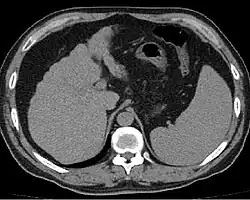

Расширенные и извитые венозные коллатерали выявляются при ангиографии, компьютерной томографии, ультразвуковом исследовании или в ходе оперативного вмешательства.